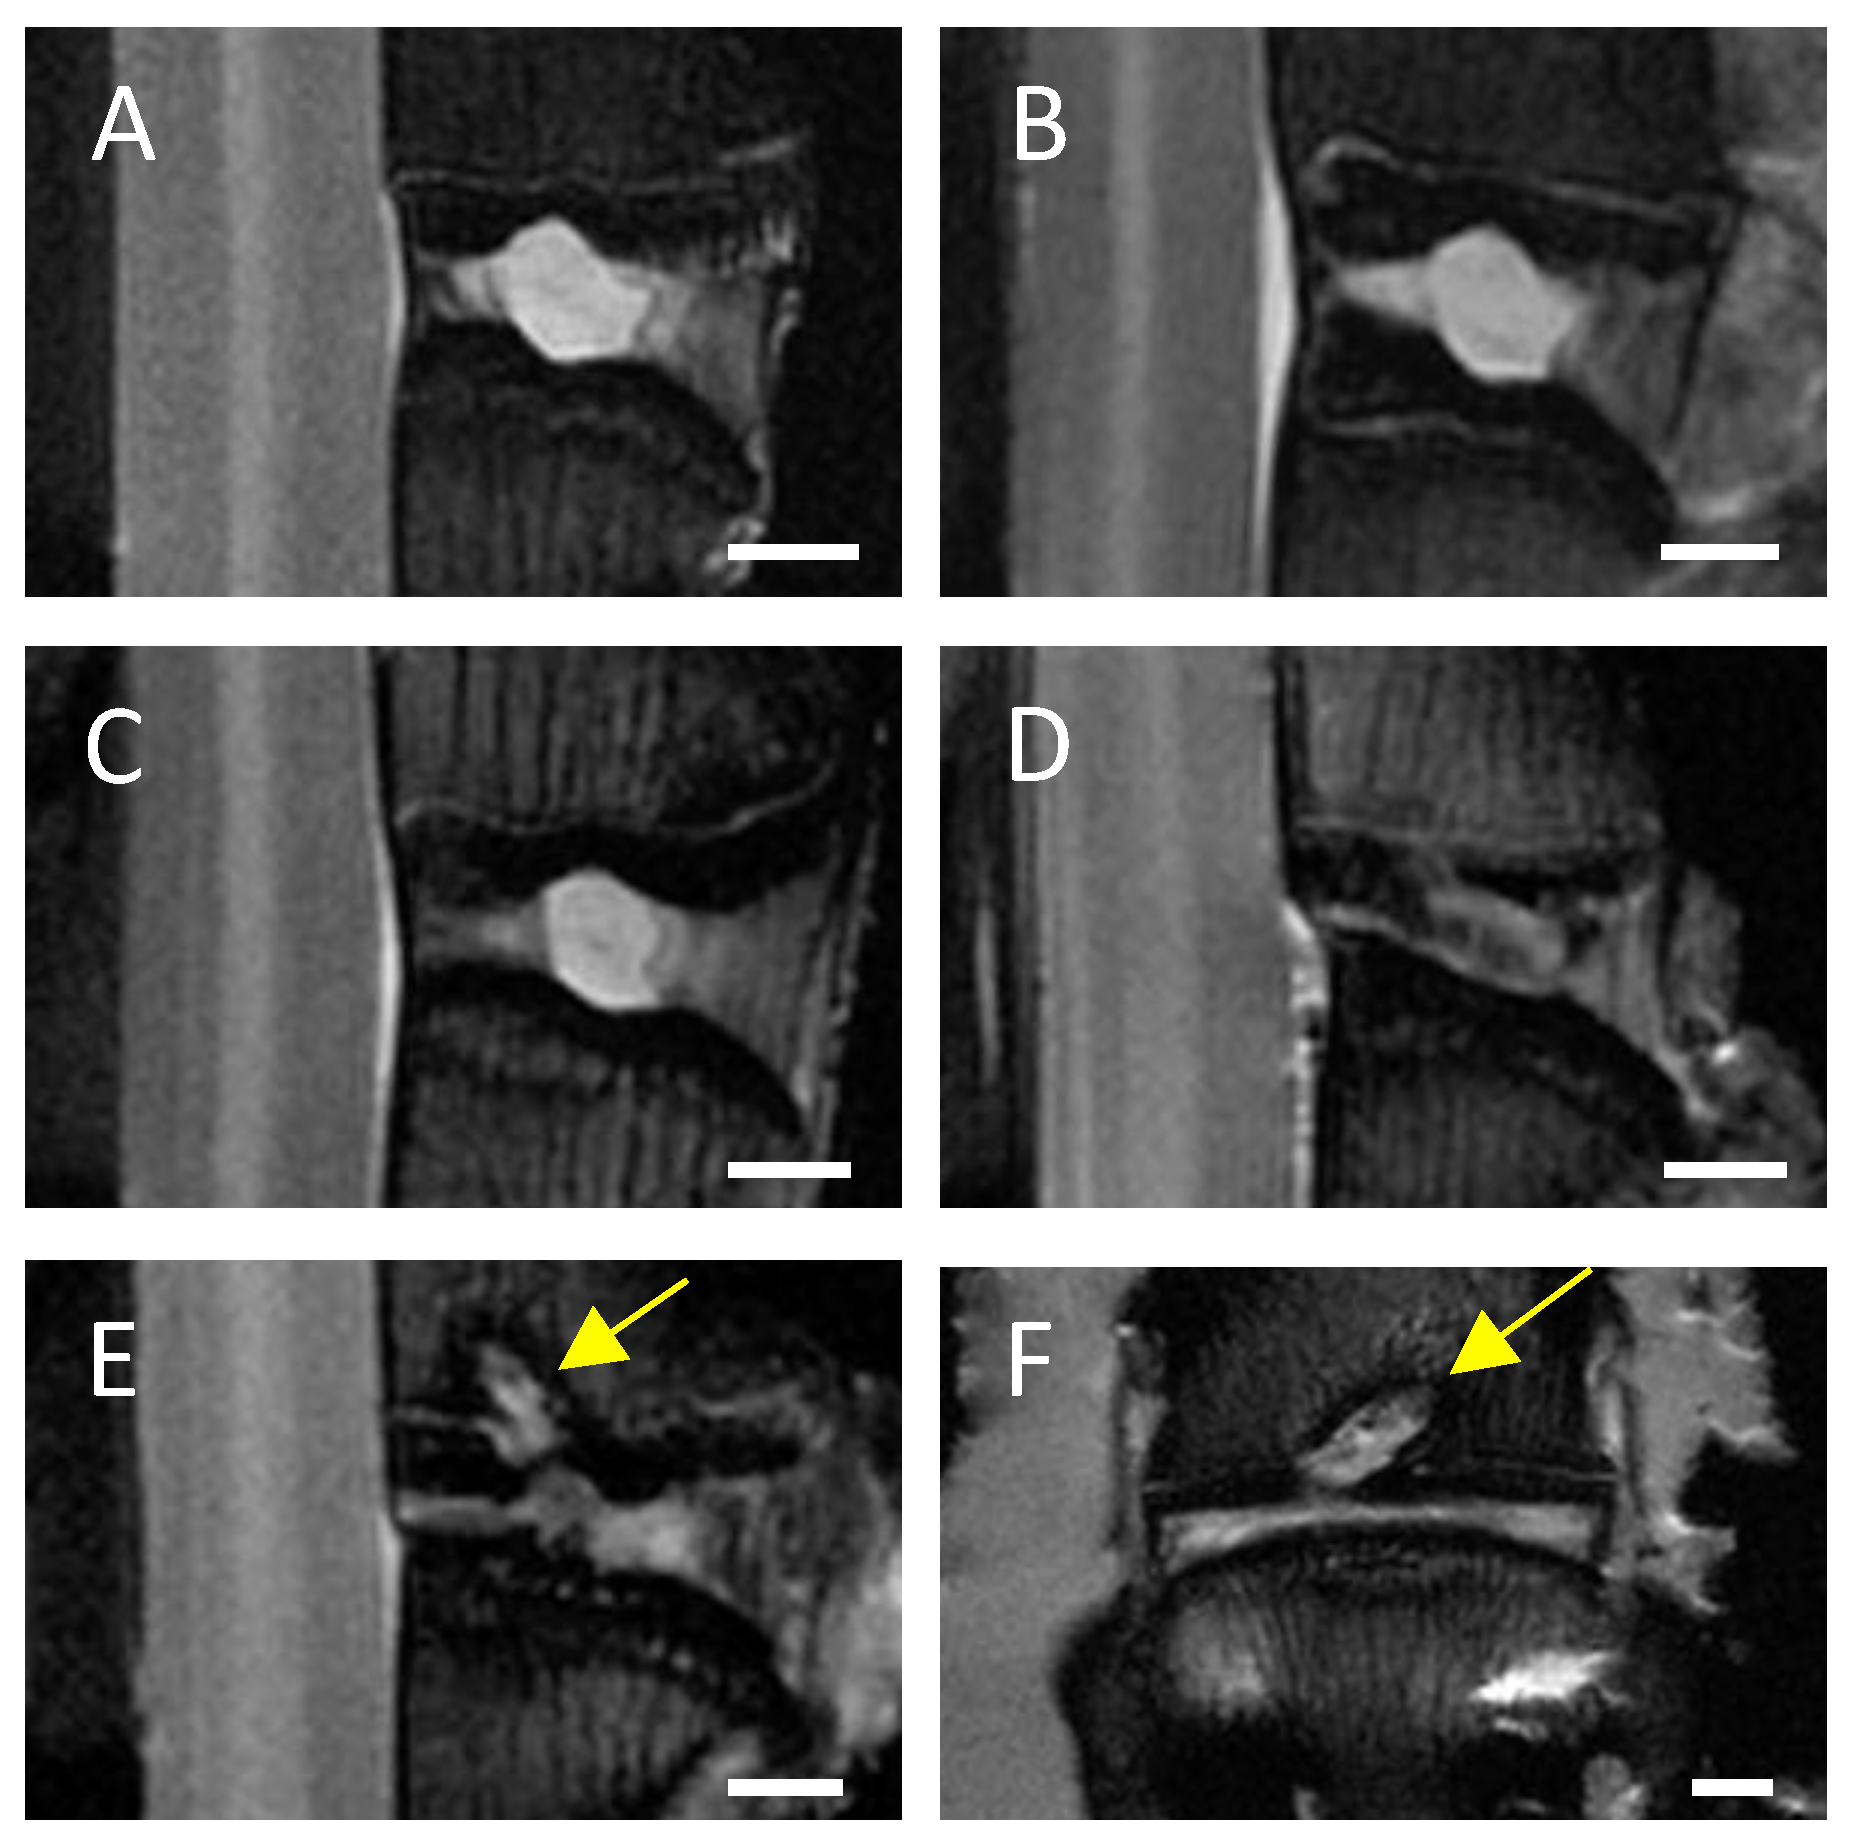

3.1. Visual Evaluation/Pfirrmann Scoring of MRI Scans Indicates a Clear Degenerative Effect of EP Drilling in IVDs of C6-Sufficient and C6-Deficient Rabbits